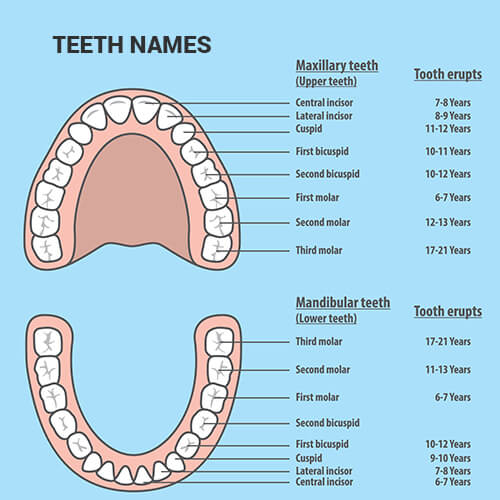

Chewing fr made my mandible longer and wider (the bone).Made my ramus longer and increases my bigonial width.My chin is also more projected.

I chewed on one side a lot more gum and now i see the changes.

I also did mewing in the other side which my jaw is more narrow.My cheekbones are higher set and more prominent.My midface shorter.And better eye hooding and better pfl.